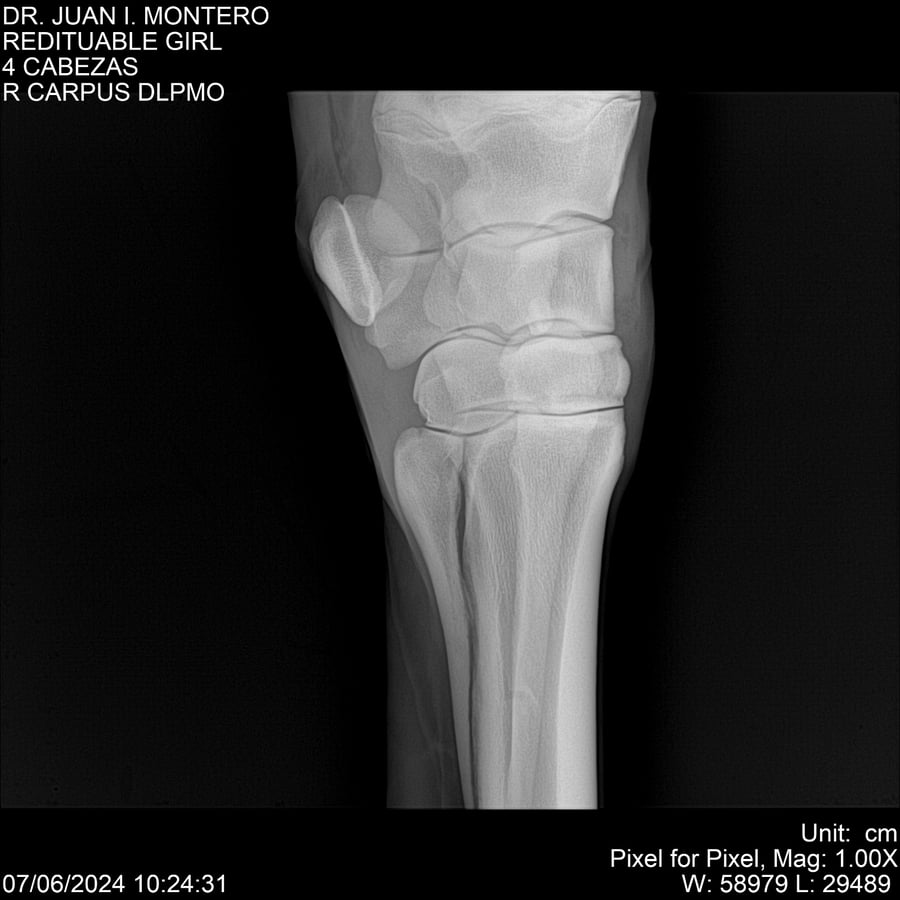

LOTE 19, REDITUABLE GIRL Lote Anterior Volver al remate Lote Siguiente Ficha Contacto Montevideo - Ficha del Lote Identificador: #281096 Categoría: Yeguarizos Montevideo - 79 Visualizaciones ClicData Contacto Empresa: Abelenda N. R., Walter Hugo Nombre*: Teléfono* : E-mail* : Mensaje Enviar Registrese gratis Este contenido Exclusivo está disponible sólo para usuarios registrados Ingresar